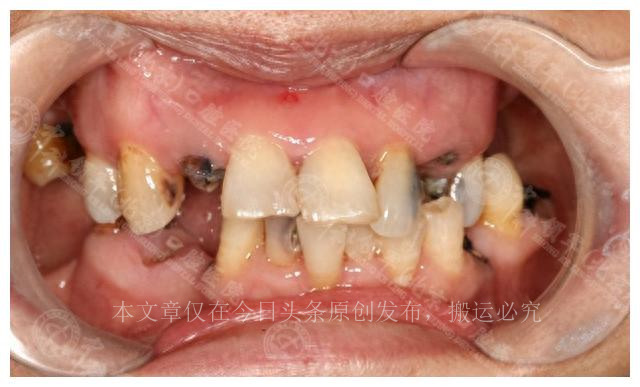

李女士,年逾六旬,身体虚弱,不仅牙齿问题困扰着她,肠胃也不甚健康,只能品尝软糯的食物。近期,李女士发现自己的牙齿变得越来越敏感,咬东西时酸软无力,而且常常感到牙痛,整夜难以入眠。这些问题虽然不是生命威胁,但却极大地影响了她的生活质量。

对于李女士来说,牙齿问题并非小事。每次吃饭都成了一场挑战,咬不动的牙齿限制了她的饮食选择,也令她备受煎熬。因此,她决定寻求专业的医疗建议,希望能够解决这一长期困扰她的问题。

李女士的牙齿问题并非小事,她的口腔健康直接关系到她的生活质量。她有11颗牙齿缺失,其中上半口缺5颗,下半口缺6颗,而剩余的牙齿已经松动,牙槽骨也有轻度吸收。